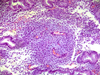

What day of the menstrual cycle is this?